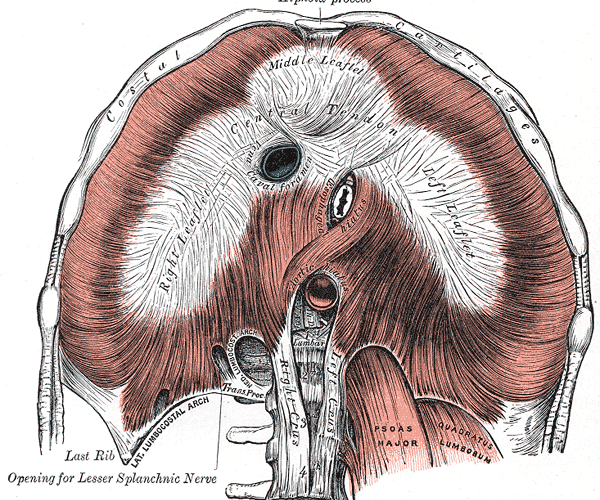

- 解剖実習:横隔膜

横隔膜の起始・停止(腱弓がある)、神経支配(二重支配、関連痛)、孔と通るものと高さ - 13:10~ エコー